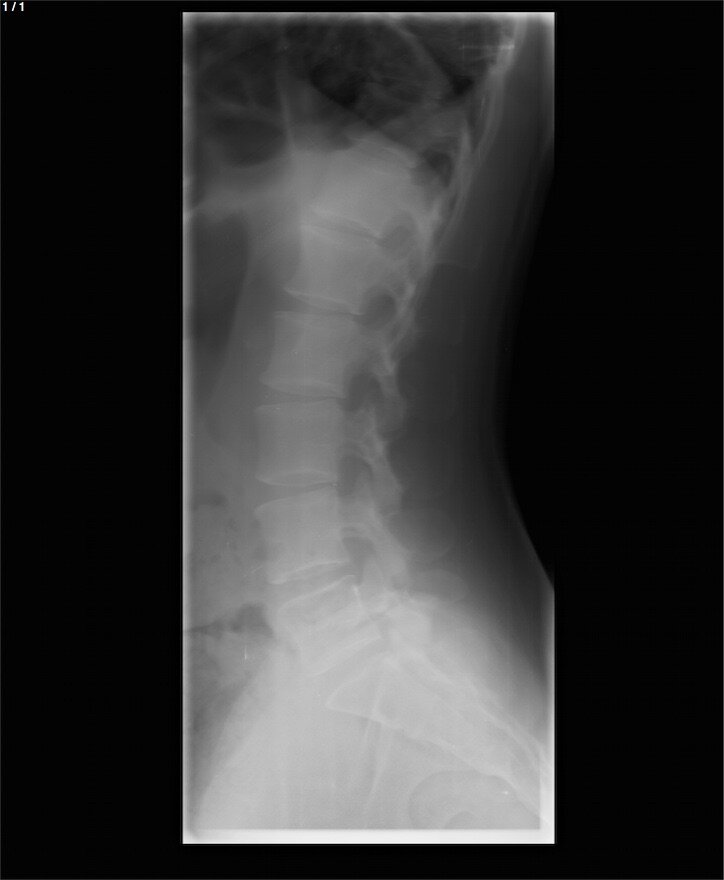

Кто разбирается в рентгеновских снимках, подскажите, здесь есть перелом крестца? Если есть, подскажите, куда конкретно смотреть?

Если есть сомнения у врача, то можно дополнительно назначить компьютерную томографию, с помощью которой получится более детально рассмотреть кости и даже построить 3D модель. Но такое решение, безусловно, принимается лечащим врачом.

Снимок крайне плохого качества и на данном снимке однозначно ответить на вопрос о переломе крестца невозможно.  В данном  случаи интерпретировать данный снимок сможет врач травматолог или рентгенолог.